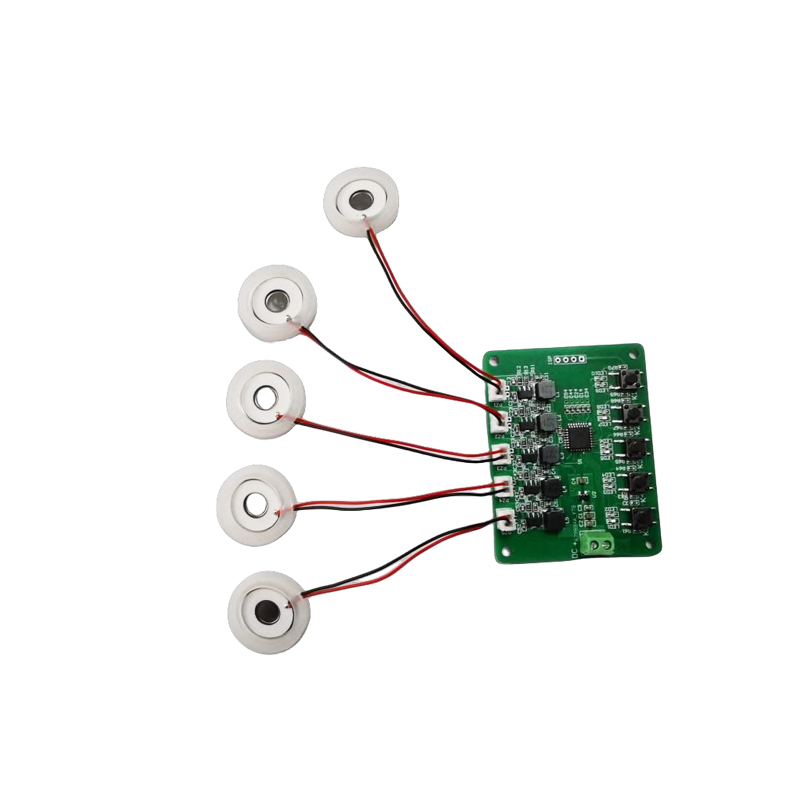

Les comprimés de nébuliseur à mailles médicales sont des composants de précision utilisés dans les dispositifs médicaux pour convertir des médicaments ou des solutions en minuscules particules d'aérosol pour le traitement de divers troubles respiratoires tels que l'asthme et la maladie pulmonaire obstructive chronique (MPOC), etc. par inhalation. La conception et le choix des matériaux de la feuille du nébuliseur sont essentiels pour garantir une administration efficace du médicament et le confort du patient. La feuille de diaphragme en acier inoxydable est percée de milliers de minuscules trous de maille de 2 à 3 µm dans la tôle d'acier grâce à une technologie de perçage laser dans un processus laser de précision, puis elle est étroitement liée à la feuille ronde en céramique piézoélectrique, qui convertit la fréquence de résonance de la feuille piézoélectrique en énergie de vibration haute fréquence via le signal de sortie de la carte de commande PCB, et décompose rapidement le médicament liquide en fines particules d'aérosol. Ces gouttelettes sont également appelées taille médiane des particules. Lorsque le pourcentage médian de la taille des particules D50 atteint > 60 % ou plus, les particules seront suffisamment petites pour pouvoir atteindre profondément les poumons jusqu'à la surface des alvéoles avec la respiration, améliorant ainsi l'efficacité d'absorption du médicament et l'effet thérapeutique. La feuille de nébuliseur à micro-mailles médicales a principalement plusieurs formes, une feuille de nébuliseur à micro-mailles en acier inoxydable, une feuille de nébuliseur médical en nickel palladium, une feuille de nébuliseur médical en polymère PI, etc. Tout ce qui précède se fait grâce à la conversion d'énergie de vibration piézoélectrique en céramique pour obtenir l'effet d'atomisation.

L'atomiseur à ultrasons est un appareil qui utilise le principe de vibration ultrasonique (conversion d'énergie) pour convertir le liquide en minuscules gouttelettes. Le principe de fonctionnement est que les propriétés piézoélectriques uniques de la céramique piézoélectrique de la décision, la pièce d'atomisation à la réception de l'excitation du signal de champ électrique correspondant, produira la fréquence d'oscillation correspondante, grâce au rôle de vibration à haute fréquence de la cavitation liquide rejetée de la surface de l'eau pour produire une sorte de particules de brouillard d'eau, atomisées avec un grand nombre d'ions négatifs et de petites particules de molécules, peuvent réaliser une augmentation de l'humidité ambiante, le rôle de l'air frais. La surface de l'atomiseur est recouverte d'émail vitreux à une température élevée de 800 degrés pour protéger les électrodes d'argent de la feuille piézoélectrique, augmenter la résistance aux acides et aux alcalis et la résistance à l'oxydation de l'atomiseur et augmenter la durée de vie de l'atomiseur. Largement utilisé dans les humidificateurs d'intérieur, les purificateurs d'air, le traitement par nébuliseur médical et les voitures de beauté, par exemple dans d'autres domaines, mais convient également aux entrepôts, aux usines, à l'humidification, à la désinfection, pour créer l'atmosphère des équipements d'humidification. Les comprimés de brumisation sont principalement utilisés dans l'humidification industrielle, la brumisation médicale, la brumisation d'aromathérapie, l'humidification environnementale, la brumisation de jardin et d'autres scènes.